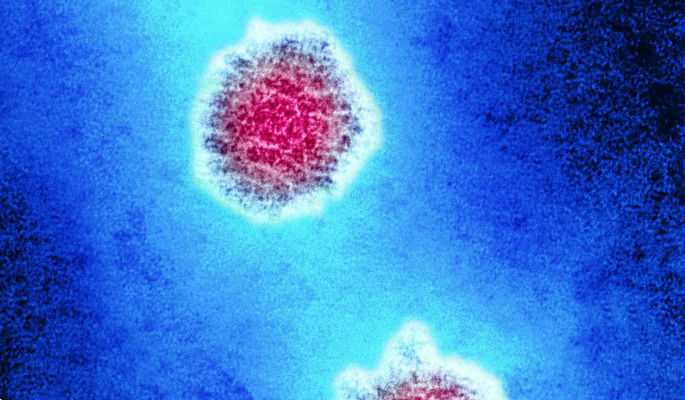

Медицинские снимки и изображения опоясывающего герпес вируса